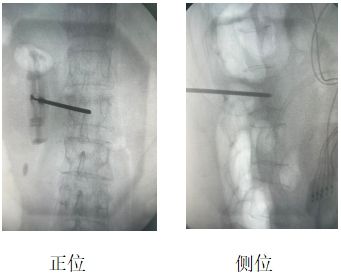

患者辛某(化名),女性,69歲,因“腰部劇烈疼痛伴活動受限2天”入院。既往有骨質(zhì)疏松癥病史,影像學檢查提示L2椎體新鮮壓縮性骨折,VAS評分8分。

當?shù)蒯t(yī)院建議外科手術(shù)治療,患者及家屬拒絕開刀手術(shù),遂來我院疼痛科。結(jié)合患者自身情況,劉康主任與科室人員經(jīng)討論,決定行“經(jīng)皮椎體成形術(shù)(PVP)”聯(lián)合“脊神經(jīng)后內(nèi)側(cè)支射頻調(diào)控術(shù)”,同時解決椎體穩(wěn)定性與神經(jīng)源性疼痛問題。

劉康主任表示,椎體成形術(shù)+脊神經(jīng)射頻調(diào)控聯(lián)合應(yīng)用,較傳統(tǒng)單一“骨水泥”植入對緩解疼痛有明顯改善。